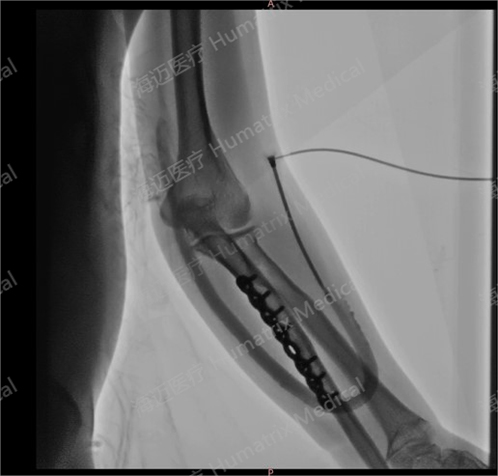

臨床試驗(yàn)患者使用LineMatrix耐邁通?生物型人工血管長(zhǎng)期血液透析,血管造影通暢。